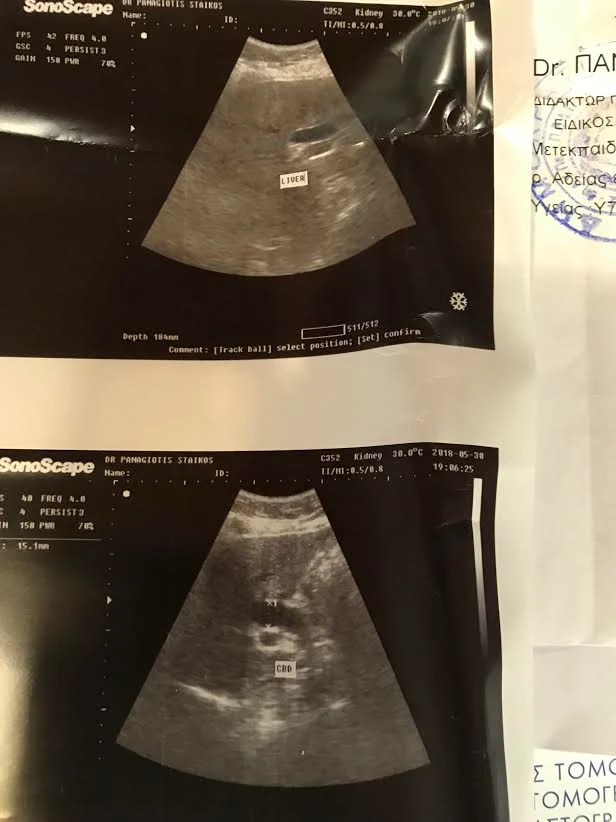

Κάνοντας όμως τον υπέρηχο διαπίστωσα, ότι είχα μεγάλη διάταση του χοληδόχου πόρου, ο οποίος πρέπει να έχει εύρος λιγότερο από 8 χιλιοστά και είχε εύρος 15,1 χιλιοστά.

Όταν η ασθενής επέστρεψε από το Αγρίνιο με το αποτέλεσμα της Μαγνητικής Τομογραφίας η όποια συμφωνούσε πλήρως με τα δικά μου ευρήματα στο Υπερηχογράφημα, επικοινώνησα με την συνάδελφο κυρία Γκάτση, την οποία παρακάλεσα να φροντίσει για να κλειστεί άμεσα το ραντεβού με τους Γαστρεντερολόγους.